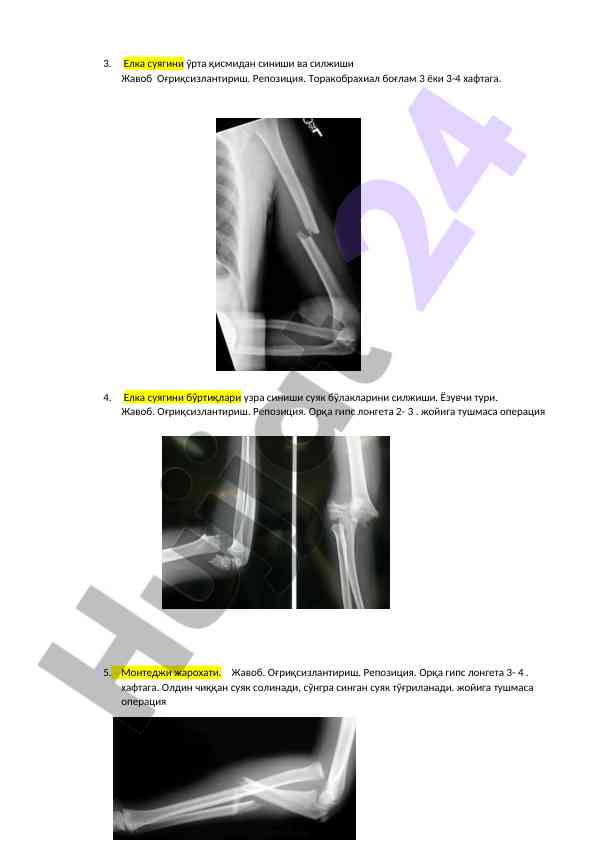

Umrov suyaqini o'rtasidan sinishi va siljishi, davolash usullari va jarohatlanishlar haqida ilmiy maqola. Bola yoshiga qarab davolash rejasi, operativ aralashuvlar va boshqa muhim jihatlar ko'rib chiqiladi.